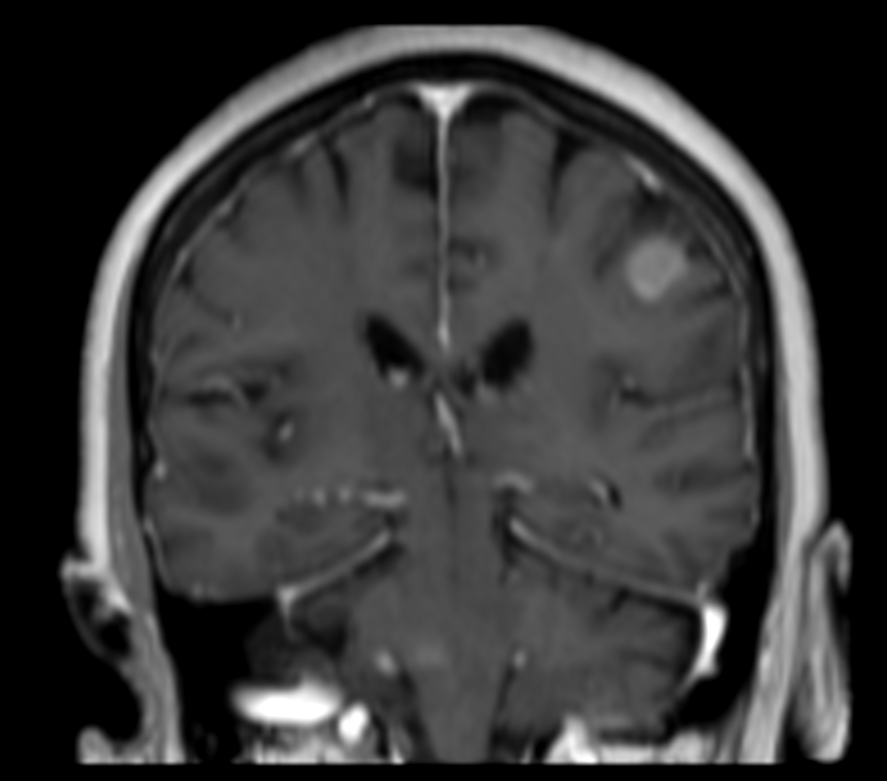

Female with one metastasis of pulmonary cancer underwent MRI simulation in the radiotherapy positioning mask on Ingenia MR-RT 1.5T before stereotactic radiation therapy with 25 Gy in 3 fractions.

3D T1w FFE (coronal reformat) post contrast